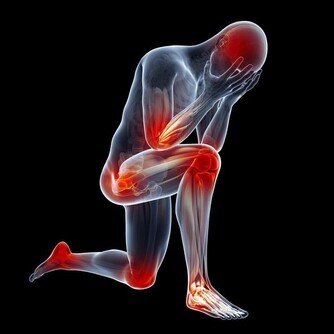

1、關節腫痛

日常生活中,很多人都會出現關節腫痛的問題,高尿酸就是其中的一個原因,如果體內的尿酸過高,就會有大量尿酸結晶,而這些結晶很難排出,只會留在我們的關節中。時間久了,就會出現關節疼痛的現象,這時建議及時去醫院檢查,查明原因,及時調理。